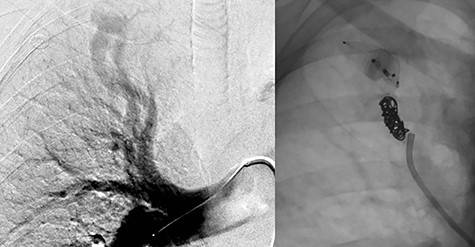

Embolization of right upper lobe PAVM with second and fourth generation Amplatzer™ Vascular Plugs and Nester® Embolization Coils.

The treatment plan consisted of embolization of the isolated simple right upper lobe PAVM followed by surgical resection of the large left-sided aneurysmal PAVMs. A surgical approach dealing with the three left-sided PAVMs was felt to be most appropriate, given that all arose from inferior lingual artery and had very large aneurysm dilation. Two days after successful embolization of the right upper lobe PAVM with second and fourth generation Amplatzer™ Vascular Plugs (Abbott Cardiovascular, Plymouth MN) and Nester® Embolization Coils (Cook Medical, Bloomington, IN), the patient underwent a left thoracotomy and lingulectomy for resection of the left-sided AVMs (Fig. 3). Before proceeding with the lingulectomy, we obtained proximal and distal vascular control with a Rummel tourniquet around the left main pulmonary artery and vessel loops around the superior and inferior pulmonary veins. The lingulectomy was performed in the standard fashion. The patient’s postoperative course was uncomplicated.